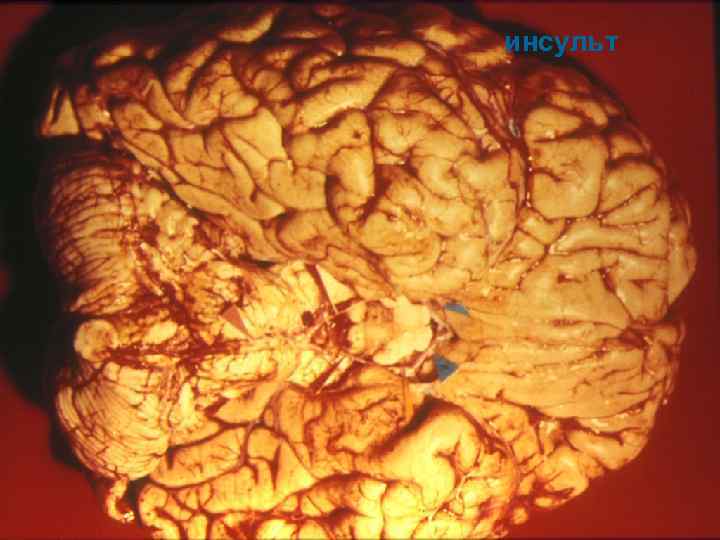

При курении артерии теряют свою эластичность, становятся плотными, ломкими, хрупкими. С годами у курильщиков просвет сосудов сужается все больше, и в конце концов это может закончиться инфарктом, инсультлм и атеросклерозом

Влияние курения на нервную систему Отрицательное влияние курение оказывает на умственную деятельность человека. У тех, кто курит, нередко возникают расстройства памяти, головная боль, бессонница, дрожание рук, снижается работоспособность, ухудшается настроение. Под влиянием курения могут развиться невриты, полиневриты, радикулиты и др. В результате курения может возникнуть спазм мозговых сосудов, сопровождающийся потерей сознания, головокружением и рвотой. У курильщиков нередко развивается склероз мозговых сосудов, вследствие чего ухудшается питание мозга, могут возникнуть эпилептические (судорожные) припадки. У них в 3— 4 раза чаще бывают кровоизлияния в мозг.

инсульт